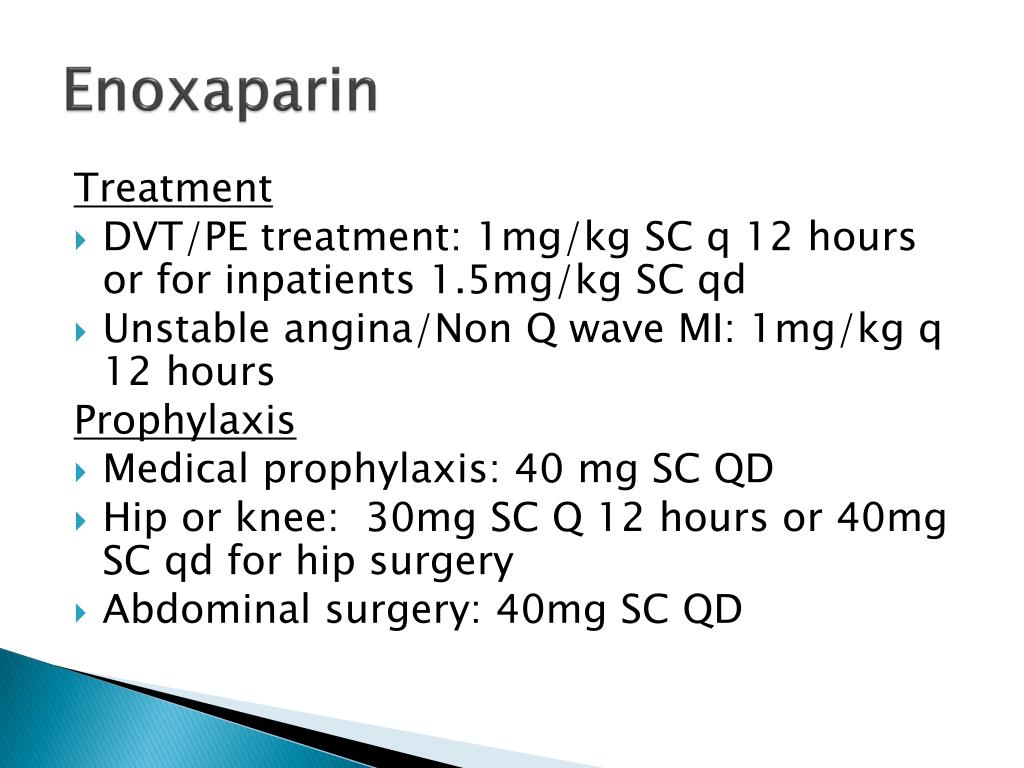

After a patient has surgery, such as hip or knee replacement or in some cases abdominal surgery, enoxaparin is often used for several days to up to a month to prevent blood clots. This medicine is also used to prevent blood clots in patients confined to bed and also for patients experiencing chest pain and heart attacks.

Uses

This medication is a "blood thinner" which helps prevent formation of blood clots. It is used after certain surgeries. Do not use this medication for prevention of blood clots (e.g., after surgery) if you have had a heart valve replacement, especially if you are pregnant. Enoxaparin may be harmful in valve replacement patients.

How To Use

Inject this medication under the skin (subcutaneously), usually once or twice daily following surgery; or use as directed by your doctor. To minimize irritation, do not repeatedly inject in the same spot; rotate the injection site. Do not inject into a muscle (intramuscularly).